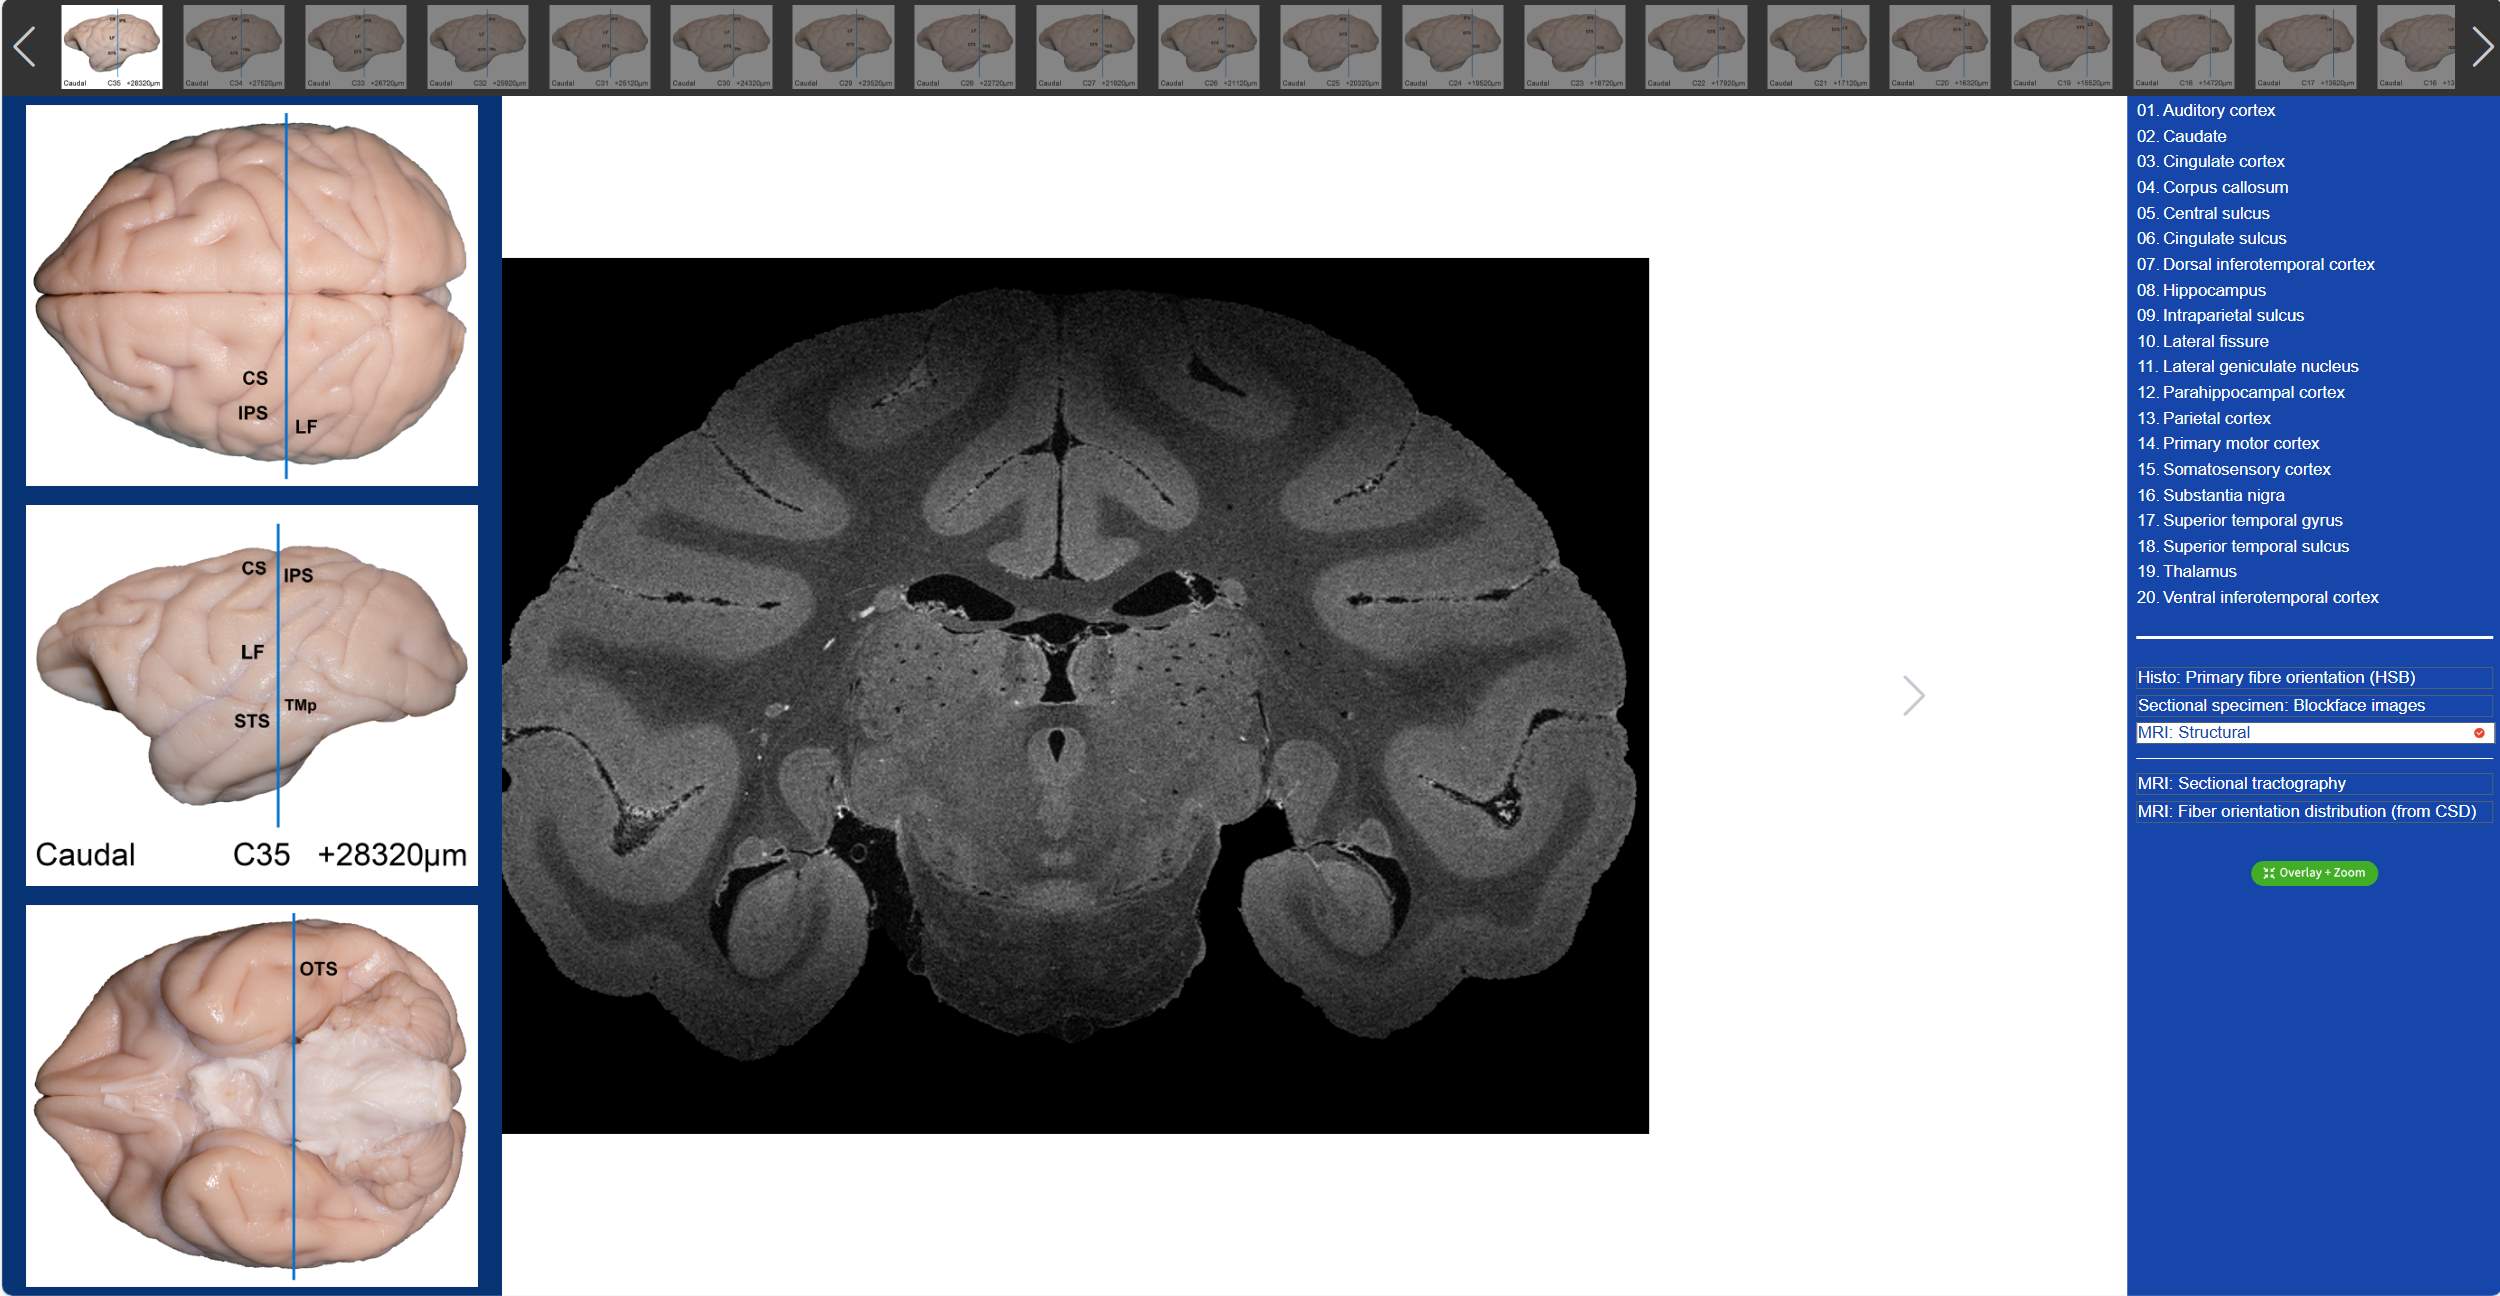

¡°¶¯ÎïÄÔÀÖÔ°¡±ÊÇÓɸ´µ©´óѧÉñ¾Íâ¿ÆÑо¿ËùÄÔ¹¦Ð§ÊµÑéÊÒ½¨ÉèµÄÒ»¸ö¿ÆÆÕÍøÕ¾£¬£¬£¬ÔËÓÃÏȽøµÄÈýάÉãÏñ¼¼Êõ£¬£¬£¬Õ¹Ê¾ÁË⨺ï´óÄÔÒÔ¼°ÈËÄÔ¡¢ÖíÄÔ¡¢ÑòÄԵȹ²Ê®¶þÖÖ¶¯ÎïµÄÄԱ걾£¬£¬£¬Ê¹ÎÒÃÇ¿ÉÒÔÍ»ÆÆÊ±¼äºÍ¿Õ¼äµÄÏÞÖÆ£¬£¬£¬ËæÊ±ËæµØÑ§Ï°ÆÊ½âѧ֪ʶ£¬£¬£¬Ö±¹ÛµÄÏàʶºÍ¸ÐÊÜ´óÄÔµÄÐÔ×´¡¢ÖʵصÈÐÅÏ¢£¬£¬£¬×èÖ¹Ö»¼ûÊ÷ľ²»¼ûÉÁÖµÄÄæ¾³¡£¡£¡£¡£ÔÚ´óÄÔÈýάչʾ½çÃæ£¬£¬£¬ÎÒÃÇ¿ÉÒÔͨ¹ýÊó±ê»ò´¥¿Ø°åÀ´Ðýת¡¢Ëõ·Åÿһ¸ö¶¯ÎïµÄÄԱ걾£¬£¬£¬´ÓÈκÎÒ»¸ö½Ç¶È¾ÙÐÐÊӲ죬£¬£¬¾ÍÏñ¸ÃÄԱ걾ÔÚÎÒÃÇÑÛǰһÑù£¡Ö±¹ÛµÄ¸ÐÊܲî±ð¶¯Îï´óÄÔµÄÐÔ×´ºÍ¾Þϸ£¬£¬£¬²¢ÓëÈËÄÔ¾ÙÐнÏÁ¿¡£¡£¡£¡£ÔÚÈËÀà´óÄÔÈýάչʾ½çÃæ£¬£¬£¬ÎÒÃDz»µ«¿ÉÒÔÏ꾡µÄÊӲ쵽ÿһÌõ¹µ»Ø£¬£¬£¬»¹¿ÉÒÔͨ¹ýµã»÷ÏìÓ¦ÇøÓòµÄ±àÂ룬£¬£¬Éó²éÆäλÖúÍÈÏÕæµÄ¹¦Ð§£¬£¬£¬´Ó¶ø¼ÓÉî¶Ô´óÄԽṹµÄÃ÷È·¡£¡£¡£¡£

ÖµµÃÒ»ÌáµÄÊÇ£¬£¬£¬ÔÚ¡°¶¯ÎïÄÔÀÖÔ°¡±À£¬£¬²»µ«¿ÉÒÔÊӲ쵽⨺ï3DÄԱ걾£¬£¬£¬»¹¿ÉÒÔ¿´µ½â¨ºïµÄÈ«ÄÔÇÐÆ¬¡£¡£¡£¡£Îâ¾¢ËɽÌÊÚÍŶӴÓͳһºïÄÔµÄÀëÌåMRI¼°È«ÄÔ×éÖ¯ÇÐÆ¬ËèÇÊȾɫ£¨LFB£©Êý¾Ý¼¯ÖУ¬£¬£¬¾àÀë800¦Ìmȡһ²ã£¬£¬£¬¹¹½¨ÁËÜöÝÍ×éÖ¯ÇÐÆ¬ËèÇÊȾɫ£¨LFB£©¡¢×éÖ¯ÇÐÆ¬ËèÇÊȾɫ-α²Ê»¯¡¢¶Ï²ã±ê±¾Í¼¡¢¸ßÇø·ÖÂÊMRI½á¹¹Ïñ¼°ÀëÌåÄÔdMRI¶Ï²ãÏËÎ¬Êø³ÉÏñºÍÏËάƫÏòÂþÑÜͼ£¨ÏÞÖÆÇòÃæ·´¾í»ý-CSD£©Áù´óģ̬µÄ¶Ï²ã±ÈÕÕͼÆ×¡£¡£¡£¡£ÎÒÃÇÖ»ÐèÒªµã»÷ÏìÓ¦µÄÆÊ½âÃû³Æ£¬£¬£¬¾Í¿ÉÒÔÔÚͼÆ×É϶ÔӦλÖÃÏÔʾ±ê¼Ç£¬£¬£¬Í¬Ê±¿ÉÓëÁíÍâÁ½´óģ̬µÄdMRIÆ«ÏòÐÔÐÅÏ¢¾ÙÐбÈÕÕ£¬£¬£¬¼«´óµÄÀû±ãÁËÈÎÄ㲩ԢĿ¡£¡£¡£¡£